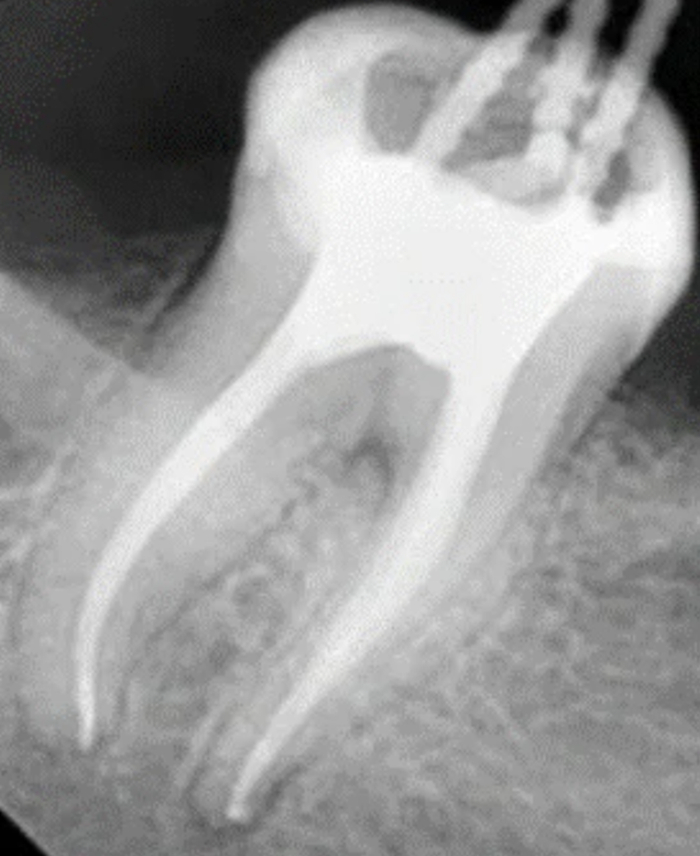

На снимке это выглядит примерно так: